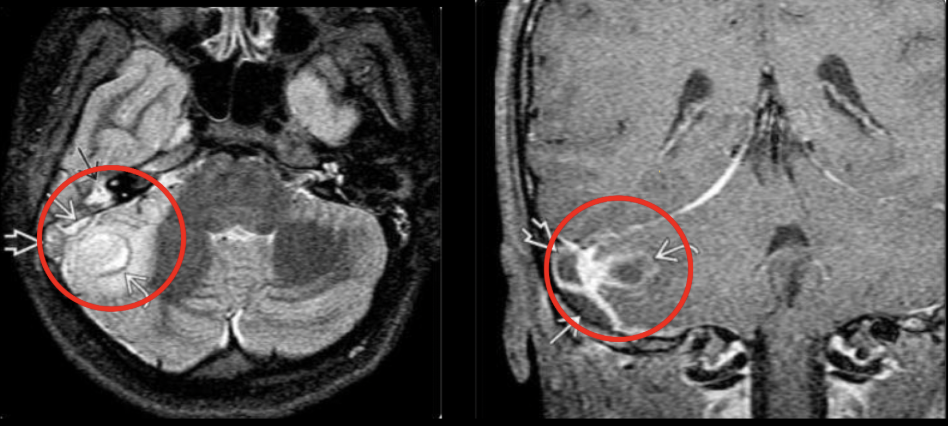

La RM está indicada en las complicaciones de la otitis media, ¿Coque veras en la secuencia T1 y T2?

T1: masa hipointensa en oído medio

T2: masa híper intensa en oído y mastoides

Diagnóstico probable

Otitis media